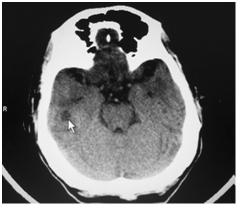

In the presence of clinical mastoiditis, a CT scan should be performed to evaluate for an unappreciated subperiosteal abscess or coalescent mastoiditis (Figure 1 & Figure 2). MRI is also useful in mastoiditis cases (Figure-3), but it is not done routinely. CT scan can demonstrate subperiosteal abscess and possibly the cortical defect in the mastoid.

Figure 1 CT scan picture showing mastoiditis changes on the left side.